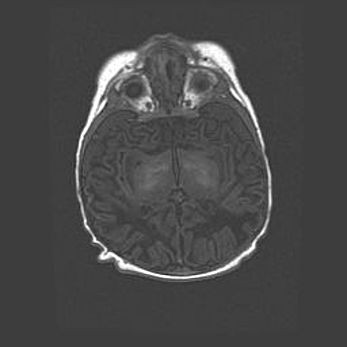

Неполная лизэнцефалия (пахигирия). Открытая гидроцефалия.

Возраст: 17 дней

Вес: 3110 г

Пол: мужской

Окружность головы: 33,5 см

Срок гестации: 35-36 недель

Лизэнцефалия—недоразвитие корковой пластинки и мозговых извилин в результате нарушения миграции нейронов коры. Поверхность мозговых полушарий гладкая. Микроскопически выявляется отсутствие нормальных слоев коры и скопление групп нейронов в подкорковом белом веществе.

Пахигирия—уменьшение числа вторичных извилин. В пораженном полушарии нервные клетки образуют толстый недифференцированный слой с неправильно расположенными нервными волокнами и группами гетеротопных клеток. Нервные клетки незрелые. Белое вещество истончено. При этом нередко аномально развит корково-спинномозговой путь.